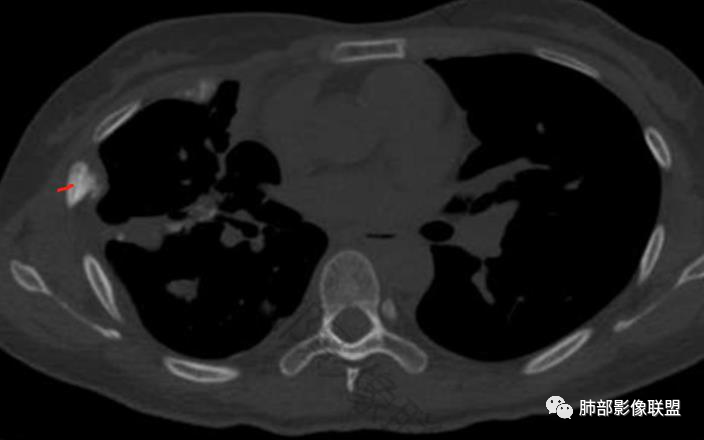

一切∮随缘:双侧胸廓塌陷,以右侧为主,右侧肋间隙狭窄,双肺上叶及右肺下叶胸膜下多发不规则肿块,密度不均匀,内部可见条片状,不规则钙化影,部分钙化不密实,双肺多发纤维索条影,似陈旧性病灶,双侧胸水,临床年轻女性,无感染症状,考虑考虑结核淀粉样变,转移性钙化,弥漫性肺骨化病。

王秀仙:双肺多发条索状及结节状病灶,部分钙化,边界清晰,双侧纵膈胸膜及双侧胸膜可见结块状及弧形软组织肿块,内见多发钙化灶,右侧胸腔塌陷,考虑结核伴淀粉样变性。鉴别胸膜间皮瘤。

丽:双肺散在索条及条片状高密度影,边界清晰,部分实变内可见钙化,支气管管壁增厚,双肺胸膜局限性增厚伴钙化,部分肋骨密度增高,首先考虑结核并淀粉样变性,鉴别转移性钙化,肿瘤样钙质沉着症,胸膜间皮瘤。

傅昌瑜:青年女性,咳嗽胸痛2月,偶有血痰。双肺上叶多发不规则肿块,密度不均匀,内部可见点状、条片状钙化影,右上肺病灶空洞,壁厚薄不均,见壁结节,与支气管关系不清,两侧胸膜增厚,见多发结节,部分结节边缘膨隆明显,结节内亦有多发钙化。上述改变常见于结核、尘肺、钙化性转移等疾病。有膨隆感的结节考虑转移可能性大。

尘缘:青年女性,痰中带血,胸痛2月,无发热盗汗,实验室检查,有贫血,总蛋白降低,血沉情况未知,肿标基本正常。影像表现:双上肺小叶间隔增厚,双侧胸膜广泛不规则增厚,胸膜下多发肿块伴不规则钙化,右侧肋骨破坏。纵隔淋巴结肿大不明显,双肺门淋巴结肿大,部分融合,分析思路:一、感染性病变,1、结核,青年女性,胸膜增厚,多发肿块伴钙化,有咳嗽胸痛,痰中带血,要考虑,但无结核中毒症状,病史仅两月却钙化太明显,肺内没有明显树芽征,存疑,2、其他感染,无炎性指标支持,白细胞不高,可能性小。二、非感染性病变,1、尘肺,胸膜增厚,钙化,胸膜下钙化性肿块,要考虑,但肺内无粉尘结节,无职业史,可能小。2、转移性钙化,无肾脏病史,无血清钙磷代谢异常指标支持,肺内间质无钙沉积改变,基本排除。三、肿瘤性病变,1、肺癌伴转移,双上肺有小叶间隔增厚,双肺门有淋巴结肿大,要考虑,但青年女性,病史两月,钙化太多太广泛,肿标基本正常,可能性小。2、骨肉瘤转移。15-30岁青年人,是骨肉瘤高发年龄,肺内多发成骨样钙化转移灶,双上肺小叶间隔增厚符合癌淋样表现,右侧肋骨破坏,要高度怀疑,需要详细询问病史及手术史。3、软骨来源肿瘤伴肺内转移,右侧肋骨虽有破坏,但无明显软骨样破坏及钙化。可能小。4、其他肿瘤伴转移,青年女性,其他恶性肿瘤能广泛发生钙化性转移的可能性小。综上所述:骨肉瘤伴右侧肋骨及胸膜转移,胸膜下转移,肺内癌淋可能最大,结核不完全除外,下一步需要,仔细询问病史,如果有骨肉瘤史,则基本确诊,如果没有,需要进一步问询呼吸系统症状,病程,以前的影像对照,了解肾脏情况,查血清钙磷指标。

这个骨窗很有价值

价值就在于这个密度

骨质破坏,但是密度增高

你对比一下髓腔

它这个髓腔密度不对,皮质也欠连续,还是以骨头为主

南边:那就是说这个肋骨是自身的病变,有成骨性骨质破坏